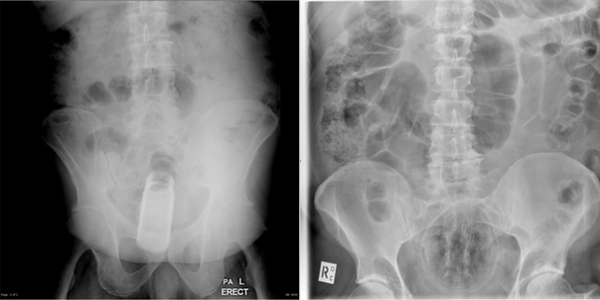

Site reúne raios-x para consulta geral de profissionais

Para pesquisas na internet, geralmente, as pessoas buscam artigos na Wikipedia. Radiologistas procuram em um site um quanto peculiar chamado Radiopaedia. A página reúne imagens de raio-x e, inclusive, mostra partes extremas (e nunca imagináveis) do corpo humano.

A página é um recurso educativo para compartilhar tutoriais e conhecimento sobre tudo que envolve o assunto de radiologia. Para aqueles que não são muito interessados (ou se surpreendem facilmente) por assuntos relacionados a medicina, no topo existe um aviso: “Esse site é dirigido para profissionais médicos e de radiologia, contém conteúdo colaborativo e materiais que podem confundir o público leigo”.

Confira algumas das imagens: